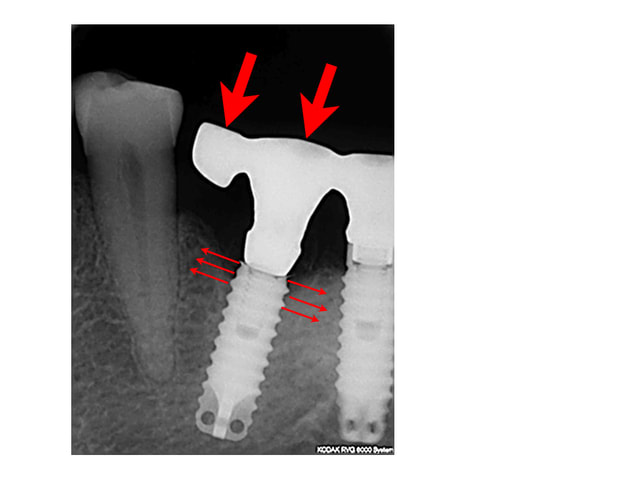

A propos de ce cas dont tu a herite je crois .

Ne penses tu pas que la fracture du ciol est lie aux tensions qui s'exerce contenu de l'inclinaison de l'implant et de l'extension mesiale

11/12/2007 à 15h41

patiente

1)édentée bilaterale

2)bruxoman(girl)

3)suite implantaire difficile...n'a pas fait le travail de l'autre coté (à l'époque je faisais confiance et j'avais accepté de monter la prothèse)

4)la supra structure s'est dévissée deux fois en 7 ans et à chaque fois je la prévenais...

posté en même temps que la radio

donc oui à toutes tes suggestions